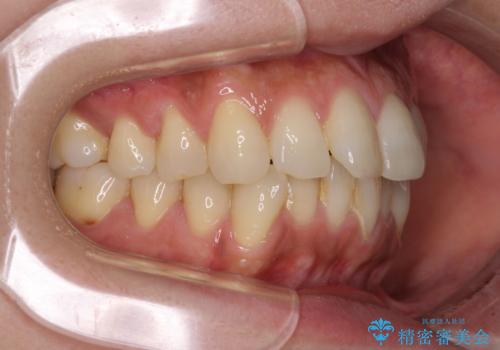

インビザラインによる矯正治療と奥歯のインプラント治療

- 全体的なデコボコと、以前抜歯した歯のスペースを閉じた部分が気になるとのことで来院された患者様です。

左上第一大臼歯を抜歯した際に、スペースを閉じたそうですが、歯が傾斜してものが挟まって不快とのことでした。

インビザライン矯正で全体の歯列と整えるとともに、左上第一大臼歯部にはスペースを作り、インプラントによる補綴治療を行うこととしました。

歯の傾斜が改善され、インプラントによるクラウンが装着されたことで、物が挟まることもなくなりました。